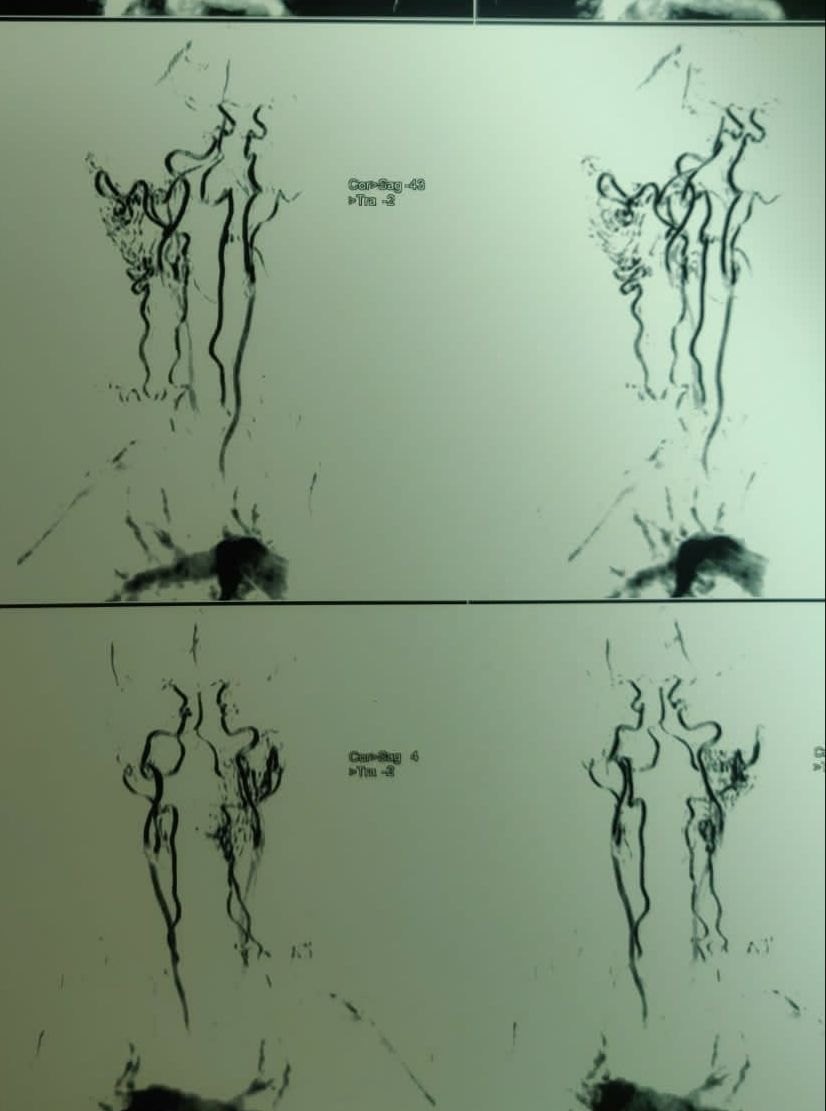

45 year old female with cavernous hemangioma

Diagnosis : INTRAMUSCULAR HEMANGIOMA NECK, i.e. in BETWEEN TRAPEZIUS, SPLENIUS CAPITIS WITH NO INTRACRANIAL EXTENSION.

Cavernous hemangioma in neck region